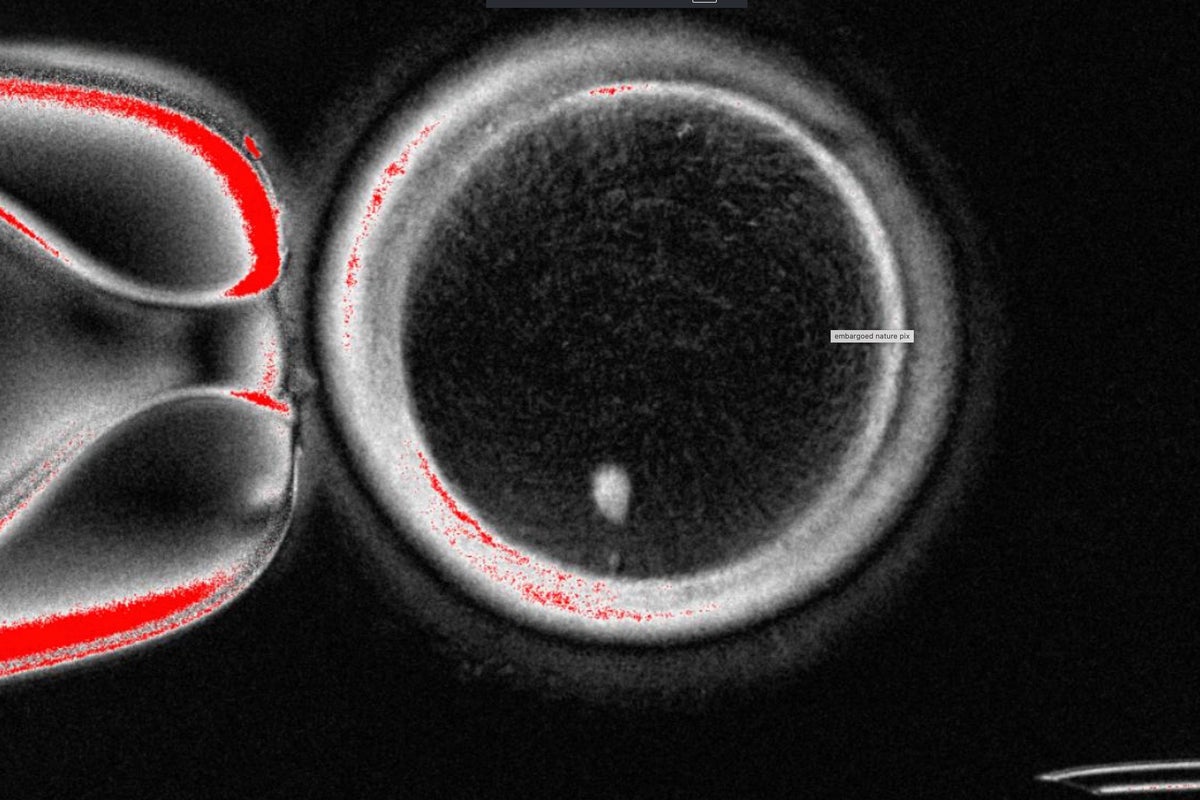

The OHSU team removed the nucleus from a human egg cell and replaced it with the nucleus from a human skin cell. But a skin cell contains two sets of chromosomes, and eggs and sperm are supposed to each contain only one set that combine during fertilization. The researchers therefore induced the egg-like cells to discard extra chromosomes, injected donated sperm and jumpstarted post-fertilization development.

About 9% lasted for six days in lab dishes, reaching the blastocyst stage of early embryo development, before the experiment was stopped.